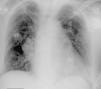

A 70-year-old woman with a permanent VVI pacemaker implanted two years previously for advanced atrioventricular block came to our emergency department due to chest pain, dyspnea and palpitations for the past two hours. An electrocardiogram performed at that time showed atrial fibrillation at 140 bpm. After electrical cardioversion, the electrocardiogram during ventricular pacing showed a right bundle branch block pattern (Figure 1). No chest X-ray was performed at that time, but a previous one was investigated (Figure 2). A transthoracic echocardiogram (Figure 3) suggested malposition of the pacemaker lead in the left ventricle with right atrial and ventricular dilatation, so a three-dimensional transesophageal echocardiogram (Figure 4) was obtained that showed the pacemaker lead passing through a 2-cm interatrial communication and the mitral valve, and finally into the left ventricle.

This complication should be considered when right bundle branch block is seen on a pacing electrocardiogram and the pacemaker lead has a posterior position on the lateral chest X-ray. A definitive diagnosis is obtained by echocardiography.